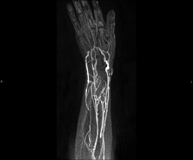

- Angio-RM extremidades superiores

Prueba diagnóstica no invasiva que consiste en el estudio de las arterias de la cintura escapular, brazo, antebrazo y mano obteniendo imágenes de alta definición anatómica mediante el empleo de un campo electromagnético y ondas de radio (con un emisor y un receptor). Es indispensable el uso de contraste intravenoso paramagnético (gadolinio). Sin embargo, no utiliza radiación ionizante. La calidad de las imágenes permite realizar reconstrucciones en 2D y 3D. Está especialmente indicado en aquellos pacientes en los que hay sospecha de enfermedad vascular de ambas extremidades, en pacientes con enfermedad vascular de ambas extremidades como mapa vascular antes del tratamiento (percutáneo o quirúrgico), como mapa vascular pre-quirúrgico en pacientes con lesiones óseas o musculares que requieran cirugía…